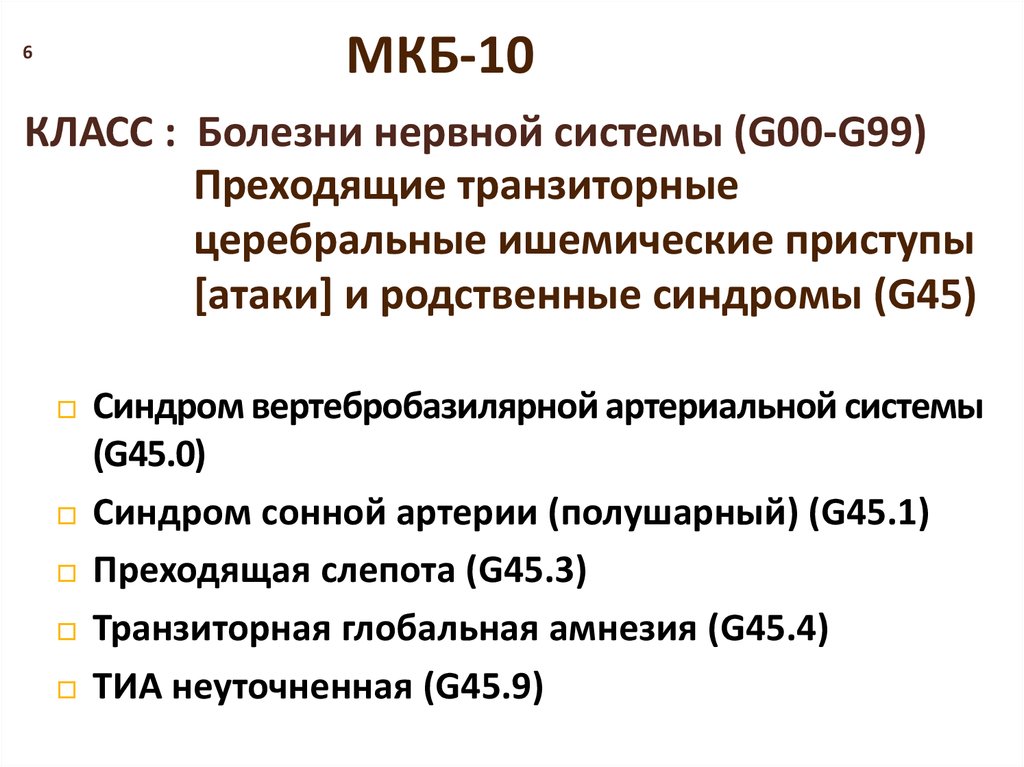

Код мкб 10 атерома головы

Код мкб 10 атерома головы 109 фото